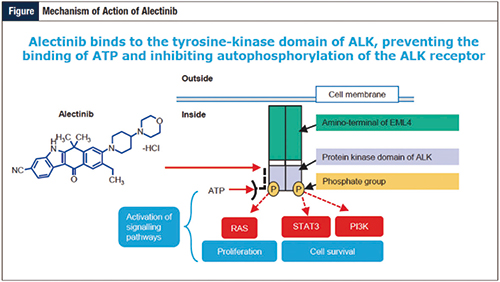

ALEX研究数据更新 Alectinib治疗PFS获益优…

ALEX研究数据更新 Alectinib治疗PFS获益优…

2019-04-02 11:30:25

美国科罗拉多大学Camidge等报告ALEX试验更新结果显示,一线治疗ALK阳性晚期非小细胞肺癌(NSCLC)时,研究者评估的Alectinib对比克唑替尼的无进展生存期(PFS)仍更长,且该疗…